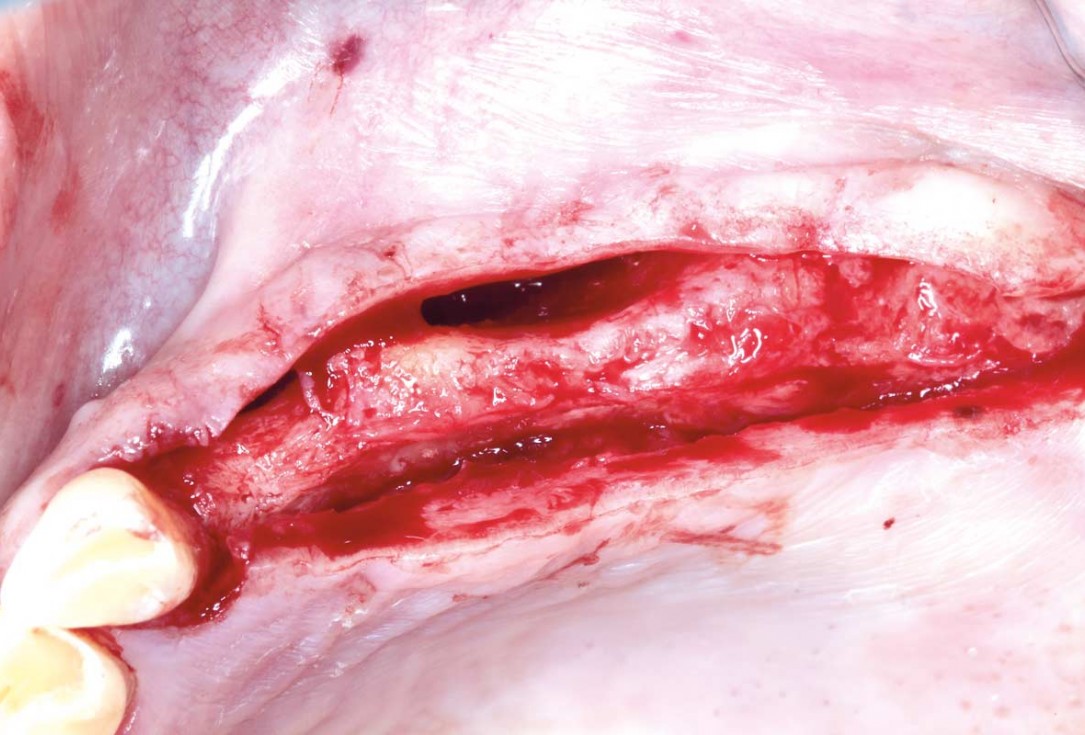

01/12 - Atrophic alveolar ridgeHorizontal ridge augmentation with permamem®, cerabone® and autologous bone chips - Dr. S. Pelekanos

Clinical situation of the edentulous distal maxilla before the surgery

Situation before augmentation, atrophic alveolar ridge